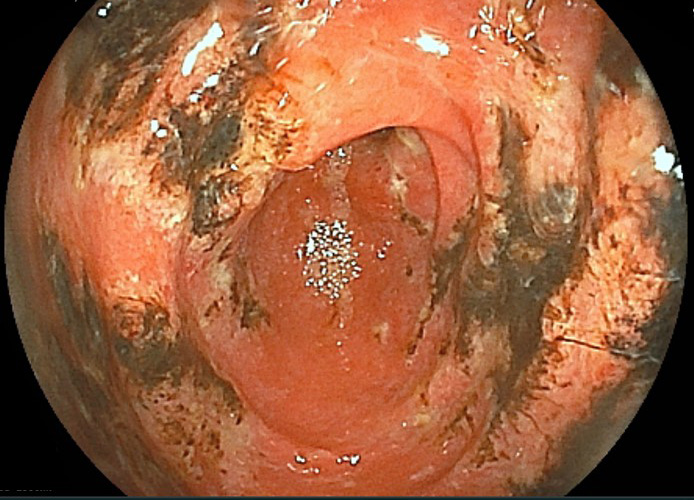

胃がん

胃粘膜の細胞が悪性腫瘍のがん細胞へと変化し、増殖していきます。日本では男女ともに胃がん患者数は減少傾向にありますが、それでもがんの患者数ではいまだに上位を占めており、年間10万人あたり約100人が日本で新たに胃がんと診断されています。国立がん研究センターが2017年に発表したがん死亡予測では、全がんの死亡数を378,000、そのうち胃がんの死亡数は47,400としています。男女とも胃がんが5位までに入っており、男性に多い傾向があります。早期には自覚症状がほとんど現れず、進行すると胃潰瘍などの胃疾患と共通の胸痛、膨満感、食欲不振などの症状を現します。早期発見のためには症状がまだない段階で定期的に胃カメラ検査を受ける必要があります。早期発見できれば適切な治療により、お仕事に支障なく完治可能です。